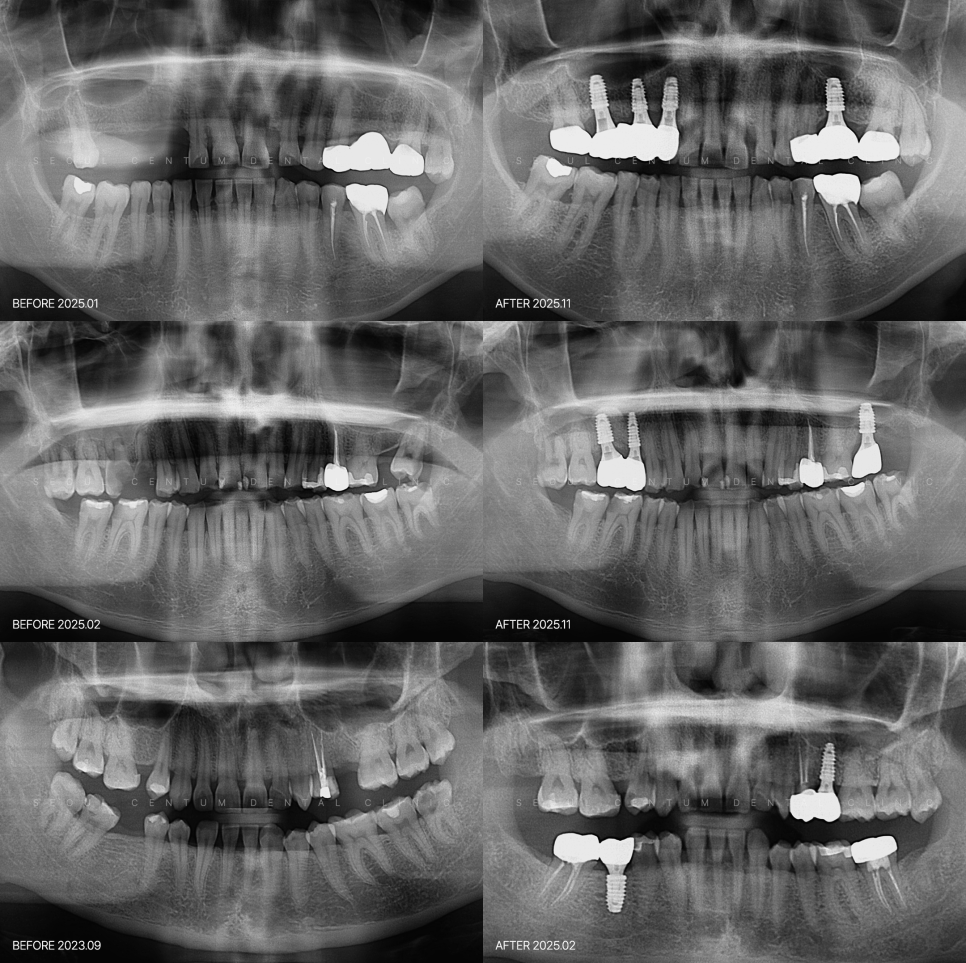

구강 검진과 파노라마 X-ray,

3D CT 등의 촬영으로

잇몸뼈의 두께와 높이, 밀도,

신경 위치 등을 면밀히 확인하고요.